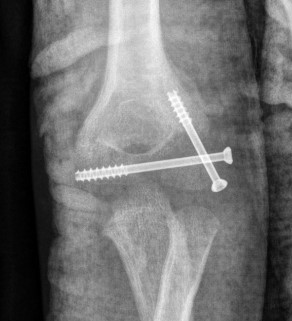

K wires v screws

Screw

- compression of fragment

- potentially less non union

- more difficult to remove

- 60 patients treated with lag screws or K wires

- no difference in outcome

- less stiffness in screw fixation due to earlier mobilisation